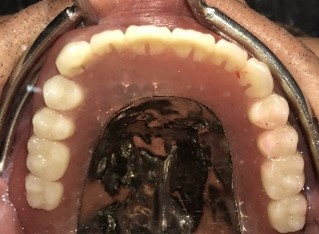

保険の部分入れ歯を入れると痛みや吐き気があり、10年以上、不具合と使いづらさを感じていたSさんが、先日当院で「マグネット式部分入れ歯」を作られました。Sさんは、「入れ歯の上あごの部分が小さく薄いので、異物感がほとんどなく、吐き気をもよおすこともありません。食事の時に入れ歯が全く動かず、よく噛めるので何でも食べられるようになりました!」と、とても喜んでくださいました。

マグネット式入れ歯は、残っている歯にバネをかけないので、見た目が自然なのも喜んでいただけるポイントの一つだと思います。部分入れ歯がはずれやすい、痛いところがある、入れ歯でしっかり力を入れて噛めない…など、その他にも気になることがある方、お気軽にご相談ください!